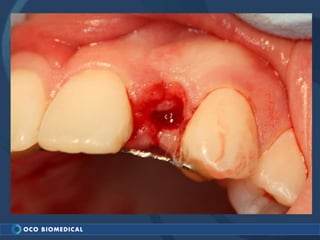

A 3.0mm dental implant was placed to replace congenitally missing maxillary lateral incisors. Dr. Tim Kosinski used a 1.8mm pilot bur and tissue punch to prepare the osteotomy site, then placed the implant by hand and seated it with a torque wrench. After ensuring the implant trajectory was within the restorative envelope, an acrylic coping was placed for temporary fabrication. At the 1 week post-op appointment, excellent soft tissue response and papilla formation were observed, and a final impression was taken to send to the lab for crown fabrication.